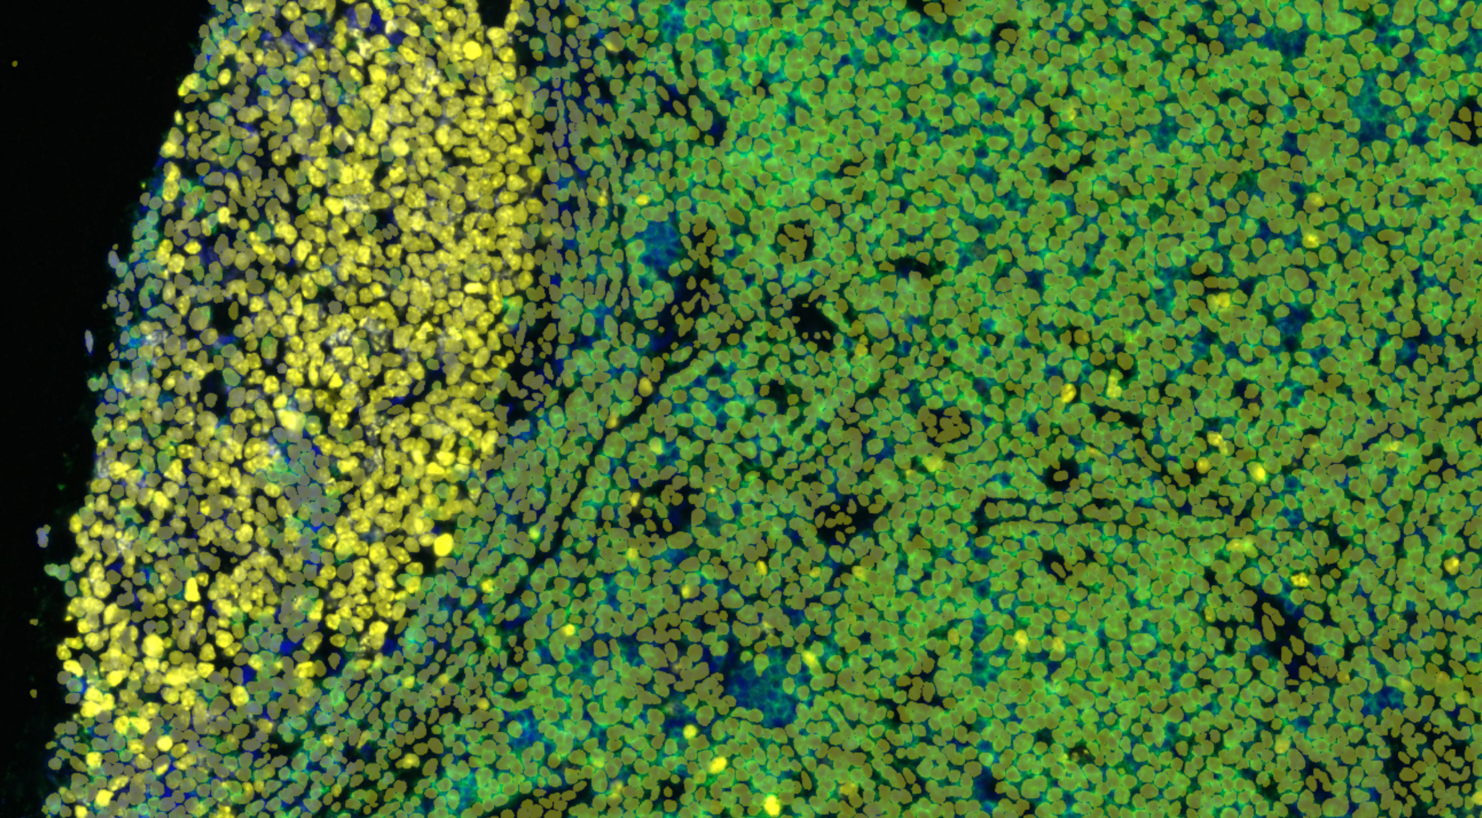

Without image analysis, information-rich multi-channel images are just images. Humans, even trained experts, are limited by–in the best case–the presence of only three-color receptors in our retina. Consequently, it becomes increasingly difficult to visually process the information coming from the 5-13 channels that are typically used with Ultivue technology, let alone considering the interactions of potentially dozens, if not a hundred, different cell types across millions of cells present in a tissue section.

AI-based image analysis gives us the opportunity to classify millions of cells and interrogate their frequency and spatial relationships in a data-driven way. This can help find out which specific immune cells need to talk to other immune cells or interact with a subset of tumor cells to predict therapy outcome, and more.

Pictured: Classified cells overlayed on IF image as image analysis detected them.